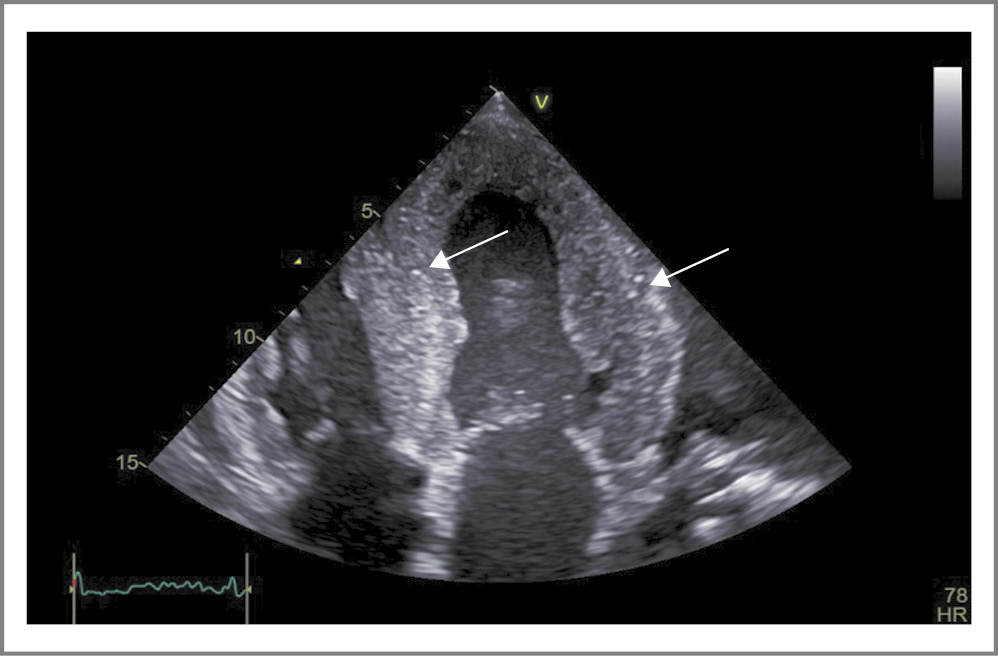

Инструментальные исследования. ЭхоКГ-исследование проведено на аппарате экспертного класса General Electric Vivid iq в ФГБНУ НИИ КПССЗ (см. табл. 1). Дополнительно, к ранее представленным данным, отмечалось снижение ФВ до 39%, а также «свечение» миокарда с гиперэхогенными включениями (рис. 2). Согласно современным рекомендациям [9] использована технология Speckle Tracking с оценкой деформации миокарда, по результатам которой выявлена типичная картина для амилоидоза сердца – выраженное снижение деформации средних и базальных сегментов ЛЖ с сохраненной деформацией верхушечных сегментов (рис. 3, 4). Показатель GLS (глобальной продольной деформации) снижен до -4,4%, через 14 дней он снизился до -3,6% (см. табл. 1). По УЗИ плевральных полостей – двусторонний гидроторакс (слева – 12 см, справа – 7,6 см). В рамках госпитализации магнитно-резонансную томографию с контрастированием гадолинием не проводили по техническим причинам.

Рис. 2. Трехмерная ЭКГ (апикальное четырехкамерное сечение). На фоне выраженного симметричного утолщения стенок ЛЖ отмечается «свечение» миокарда с гиперэхогенными включениями – глыбками амилоида (указаны стрелками)

Fig. 2. Three-dimensional echocardiography (apical four-chamber section). Against the background of a pronounced symmetrical thickening of the walls of the left ventricle, there is a glow of the myocardium with hyperechoic inclusions – lumps of amyloid (indicated by arrows)